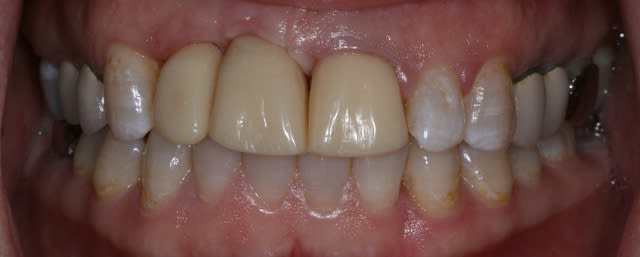

Bon ben j'ai implanté avant d'avoir refait la 21. Du coup j'ai mésialé la pose de 11 pour compenser la distalisation de 21.

Au final je n'ai pas fait de greffe osseuse... et j'ai réalisé une technique de rouleau sur 11-12 mais je reste un peu court à mon goût.

J'ai mis en place des transitoires sur 11-12-21 pour temporiser 3 mois pour voir la maturation des tissus mous.

Je réaliserai dans un second temps des piliers procera.

Je mets quelques photos de la patiente au cab et du prothèsiste d'Epinal.

La vraie difficulté a été de retrouver le milieu incisif pour déterminer la position des implants.

On avance dans le cas, j'ai revu la patiente hier.

Elle est satisfaite et moi pas vraiment, comme quoi...

Elle ne veut pas faire de chir mucco gingivale et accepte éventuellement que je fasse une petite chir d'élongation coronaire sur 21 car elle trouve cela surperflux.

Tristesse et difficulté des sourires gingivaux !

J'avais bien raison de me méfier au départ...

Bon finalement je vous poste le cas terminé.

La prochaine fois je ferrai une greffe d'apposition comme j'avais pu le préssentir... Ca me permettra de garder les papilles.

A la prochaine séance je gomme la coloration mésiale de 12, c'est promis ;+)

Un cas pas évident... l'important est que la patiente soit contente à la fin.